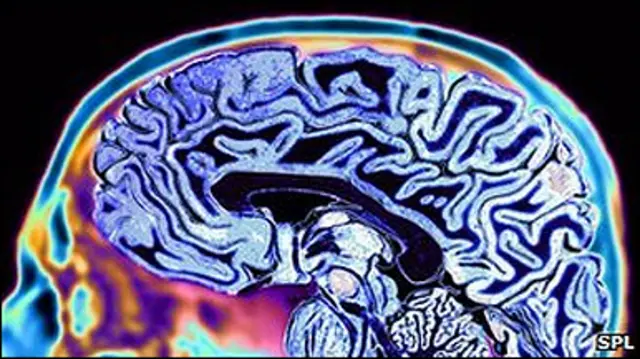

Америкалик тадқиқотчилардан бири тушларни электрон усулда ёзиб олиш ва таъбирлашни режалаётганини маълум қилган. "Nature" журналида чоп этилган мақолада тадқиқотчилар юқори даражали мия фаолиятини ёзиб олишга қодир тизим яратганларини ёзишади.

Моран Серф ўзининг дастлабки тадқиқотларига таяниб, маълум мия ҳужайралари ёки нейронлар фаолияти муайян ашёлар ва тушунчаларга боғлиқ бўлишини даъво қилади.

Кўнгиллиларга қатор тасвирларни кўрсатиш билан доктор Серф ва унинг ҳамкасблари ҳар битта ашё ва маълумот учун масъул бўлган муайян нейронларни аниқлашга муваффақ бўлишган.

Хуллас, доктор Серф қайси нейрон, қайси пайт фаоллашганига қараб, "мижознинг миясини ўқиш" мумкинлигини айтади.